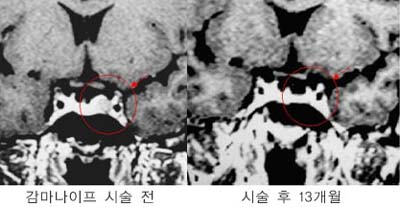

û½Å°æÁ¾¾ç

¿ìÃø

û½Å°æÁ¾¾ç ȯÀÚÀÇ MRI »çÁø. °¨¸¶³ªÀÌÇÁ

¹æ»ç¼±¼ö¼ú 4³â ÈÄ Á¾¾çÀÇ Å©±â°¡ ÇöÀúÈ÷

°¨¼ÒÇÏ¿´À¸¸ç ½Ã¼ú ÈÄ 10³â° ¸ðµÎ ¿ÏÄ¡µÇ¾ú´Ù.

Å©±â°¡

Å« ¾ç¼ºÁ¾¾ç(û½Å°æÁ¾¾ç)ÀÇ °æ¿ì ¼ö¼úÀû

Ä¡·á·Î¼ ¿ÏÀüÀûÃâÀÌ µÇÁö ¾ÊÀº ³²Àº Á¾¾ç¿¡

°¨¸¶³ªÀÌÇÁ ¹æ»ç¼± ¼ö¼úÀ» ½ÃÇàÇÏ¿© ¿ÏÄ¡µÊ